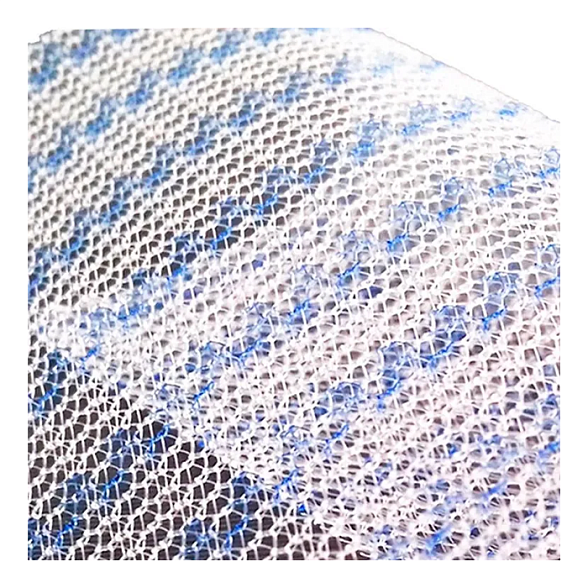

Эндопротез-сетка (сетка хирургическая) полипропиленовый для восстановительной хирургии ЭСФИЛ лёгкий, 8х12 см, Линтекс

Эндопротез-сетка полипропиленовая ЭСФИЛ лёгкий для восстановительной хирургии

Эндопротез-сетка ЭСФИЛ лёгкий от компании «Линтекс» — это современное и надежное решение для пластики грыж и восстановления целостности мягких тканей. Изделие представляет собой полипропиленовую сетку, специально разработанную для обеспечения прочной и долговечной поддержки в области хирургического вмешательства.

Ключевой особенностью данной модели является её «лёгкая» конструкция. Это означает, что сетка изготовлена из тонкого, но высокопрочного полипропиленового мононитяного материала с пониженной плотностью. Такой подход минимизирует количество имплантируемого инородного материала, что способствует лучшей интеграции с тканями организма и снижает риск послеоперационного дискомфорта для пациента.

- Оптимальная интеграция: Макропористая структура (размер пор более 1 мм) позволяет фибробластам и коллагеновым волокнам свободно прорастать через сетку, обеспечивая её надежное закрепление и естественное укрепление тканей.

| Тип плетения | Макропористая, монофиламентная сетка |

| Цвет | Белый / синий (для удобства ориентации на операционном поле) |